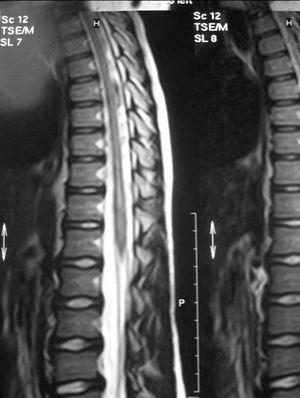

RM craneal: atrofia cerebelosa con leve aumento de IV ventrículo. Resto, normal. RM espinal: dilatación hidrosiringomiélica en médula dorsal y lumbar (fig. 1).

Figura 1.RM axial que muestra dilatación siringomiélica a nivel dorsolumbar.